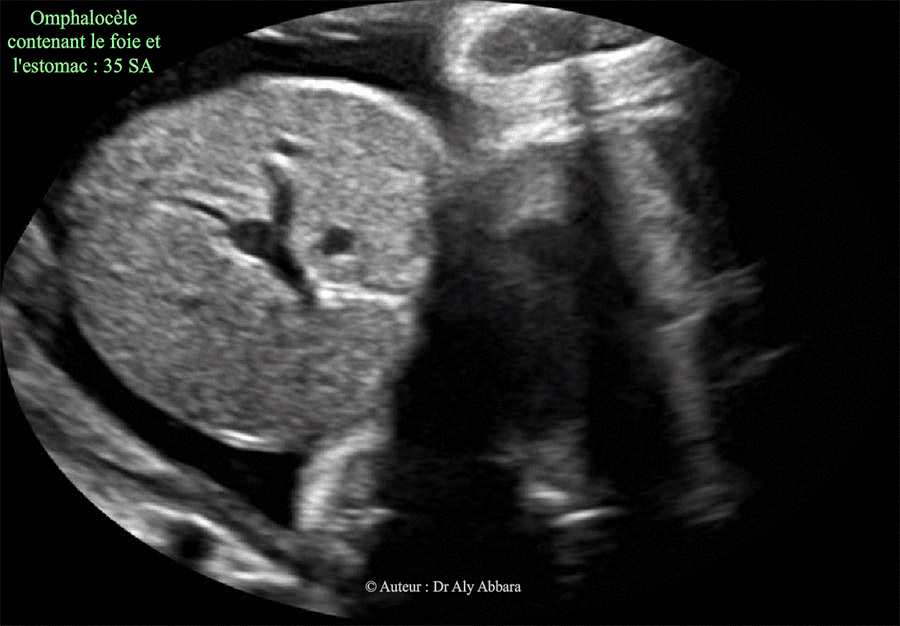

| Omphalocèle contenant le foie - Grossesse de 35 SA Coupe échographique abdominale transverse haute Aucune anomalie morphologique associée Caryotype fœtale normal (46, XX) |

| Auteur : Dr Aly Abbara Mise à jour : le 21 Novembre, 2020 |